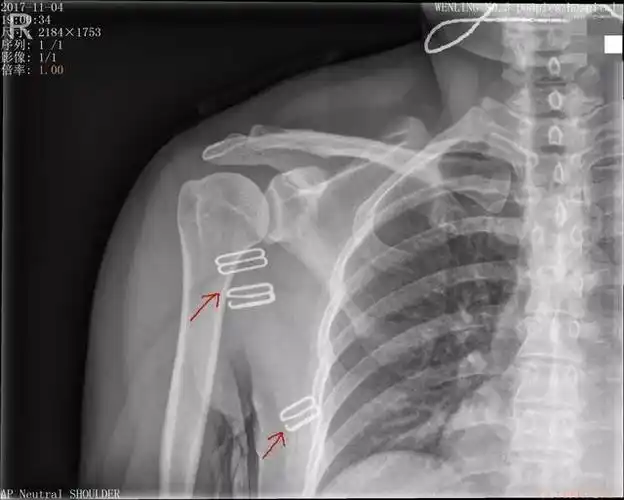

写美篇这是病人在医院拍的右肩关节x线片,相信好多人看不明白是怎么

中年女性,发现右肩关节占位2天.有特征,有细节---(有结果)